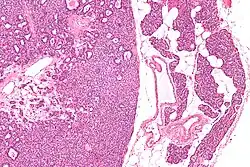

Adenoma de paratireóide é um tumor benigno da glândula paratireóide que geralmente causa hiperparatiroidismo.[1]

Um ser humano normalmente tem quatro glândulas paratireoides, localizadas por atrás da tireóide, no pescoço. A paratireoide secreta hormônio da paratireóide (PTH), que aumenta a concentração de cálcio no sangue (calcemia), ao induzir a liberação de cálcio dos ossos para o sangue e ao induzir os rins a reabsorverem o cálcio para evitar sua excreção. Quando um adenoma de paratireoide causa hiperparatiroidismo, mais hormônio da paratireóide é secretada, causando uma concentração elevada de cálcio no sangue (hipercalcemia).[2]